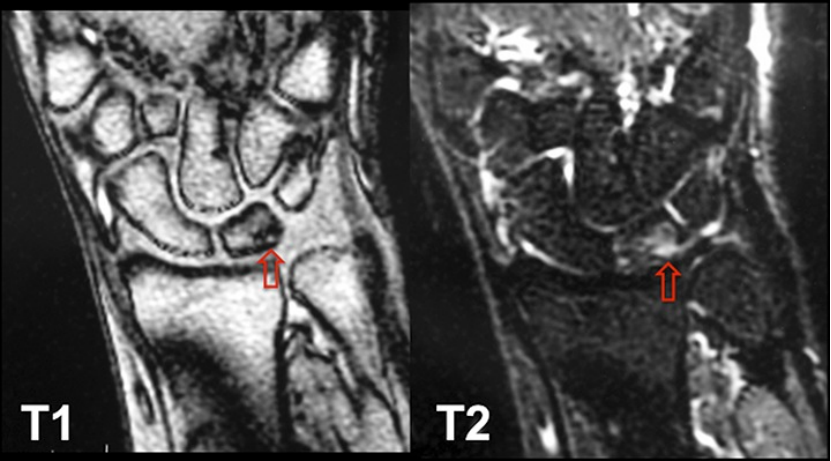

图5-A、5-B和5-C 一名37岁患有特发性尺骨撞击综合征并接受阶梯状尺骨短缩截骨术的女性患者。图5-A 术前旋前握拳位X线片。图5-B 术后12周旋前握拳位X线片。图5-C 阶梯状尺骨短缩截骨术后12周侧位X线片。

在透视下确认尺骨短缩量合适、截骨复位良好,且钢板螺钉位置不影响腕关节旋前、旋后及尺偏活动(无尺骨与腕骨接触撞击征象)。